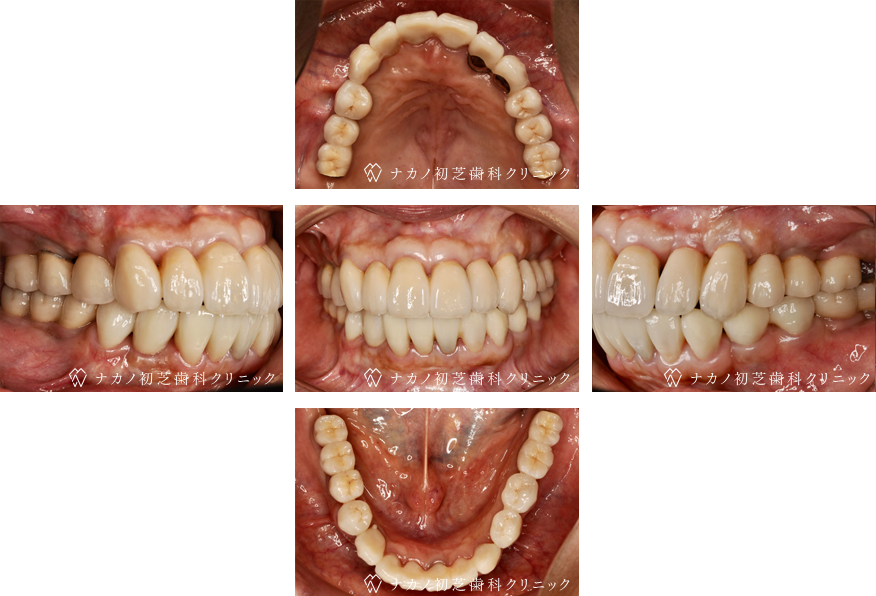

インプラント・13本 (60代女性)

BEFORE

AFTER

年齢 60代女性

治療内容 インプラント治療13本(骨造成の併用)

インプラント治療とは、歯を抜いた所にチタン製の人工歯根を埋入し、その上に歯を入れる方法です。骨を増やすことで、より審美的に治療が出来ました。費用 1本 400,000円(税込 440,000円)

リスク・副作用

腫れ・疼痛・違和感を感じるなどの症状を生じることがあります。